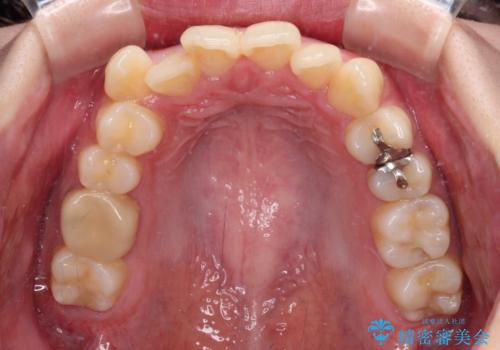

- 八重歯やクロスバイトを気にして来院された患者様です。

口元の突出感はありませんでしたが、デコボコが強く、非抜歯矯正とすると出っ歯仕上がりとなる可能性があったため、上下左右の第一小臼歯4本を抜歯し、ワイヤー装置にて矯正治療を行うこととしました。

デコボコがスッキリするだけでなく、口元の突出感も少し改善され、満足のいく仕上がりとなりました。